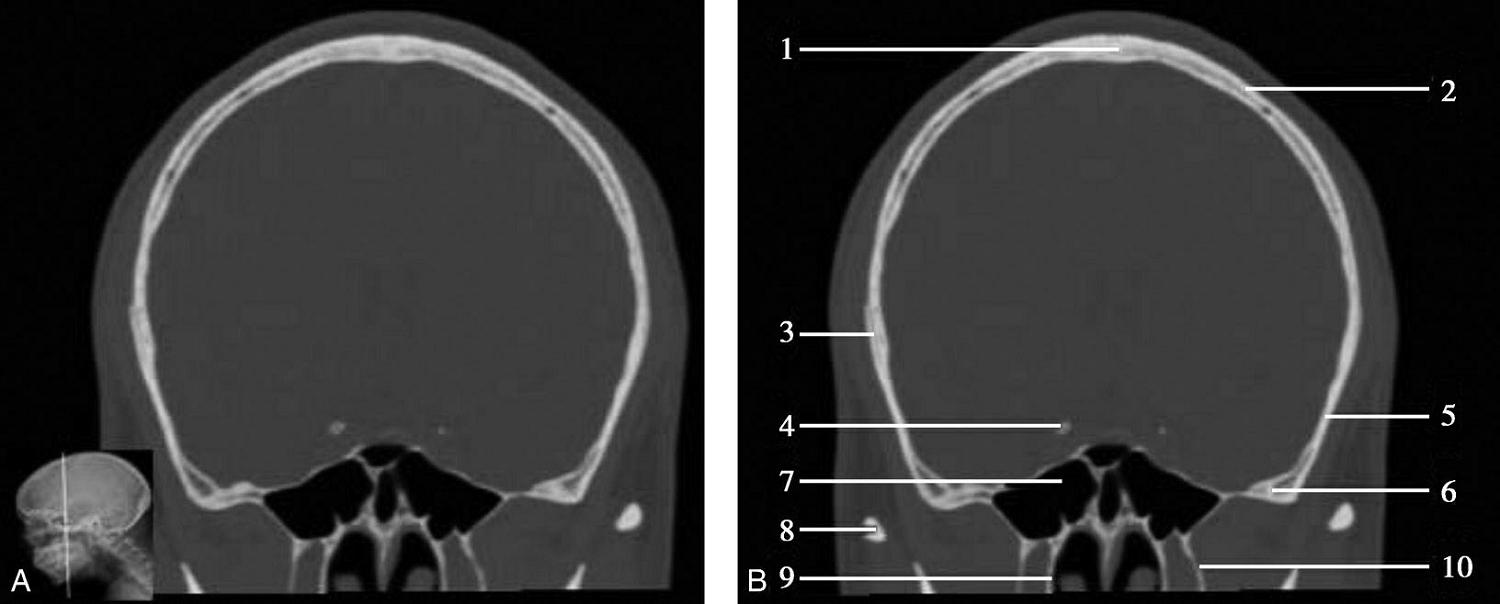

图1-2-2 颅底层面(骨窗)

A.横断面;B.横断面标注

1.鼻骨;2.筛窦纸板;3.颧骨眶突;4.翼腭窝;5.蝶骨大翼;6.卵圆孔;7.破裂孔;8.颞骨颧突;9.棘孔;10.斜坡;11.颞骨岩部;12.乳突;13.颈静脉孔;14.枕乳突缝;15.枕骨;16.枕内隆凸

层面前部呈开口向前的“V”字形,正中为鼻中隔,向两侧依次为筛窦和眼眶,眼眶内前部为眼球,后部为眶脂体。翼腭窝位于眼眶后部,窝内含有脂肪并有上颌神经通过。层面中部为蝶骨体,蝶骨体中部可见含气蝶窦,蝶窦后方为枕骨基底部,两者呈前后关系,其上面构成斜坡。蝶窦两侧为蝶骨大翼,其后外侧缘处由前向后可见卵圆孔和棘孔,分别有下颌神经和脑膜中动脉通过。斜坡外侧、岩骨尖前方为破裂孔。蝶骨大翼与眶外侧壁的颧骨借颧弓相连,颧弓和蝶骨大翼之间有咬肌及颞肌。层面中部外侧为外耳道。颞骨岩部呈“八”字形,相互之间借破裂孔软骨、蝶岩软骨结合和岩枕软骨结合连接。岩部后外侧的乳突部内可见乳突小房,乳突部与枕骨相接。岩骨后部可见颈静脉孔,内有颈内静脉、舌咽神经、迷走神经和副神经通过。层面后部为颅后窝,其内可见延髓,延髓前方为延髓前池,内有椎动脉,后外侧为小脑半球下部,后方为第四脑室、小脑扁桃体及小脑蚓部。

破裂孔、卵圆孔、棘孔及斜坡等均为重要的解剖结构,临床常见疾病如鼻咽癌常侵犯上述结构(图1-2-3)。颈静脉孔区较常见的肿瘤为颈静脉球瘤,常伴有颈静脉孔及其邻近骨质的破坏(图1-2-4)。